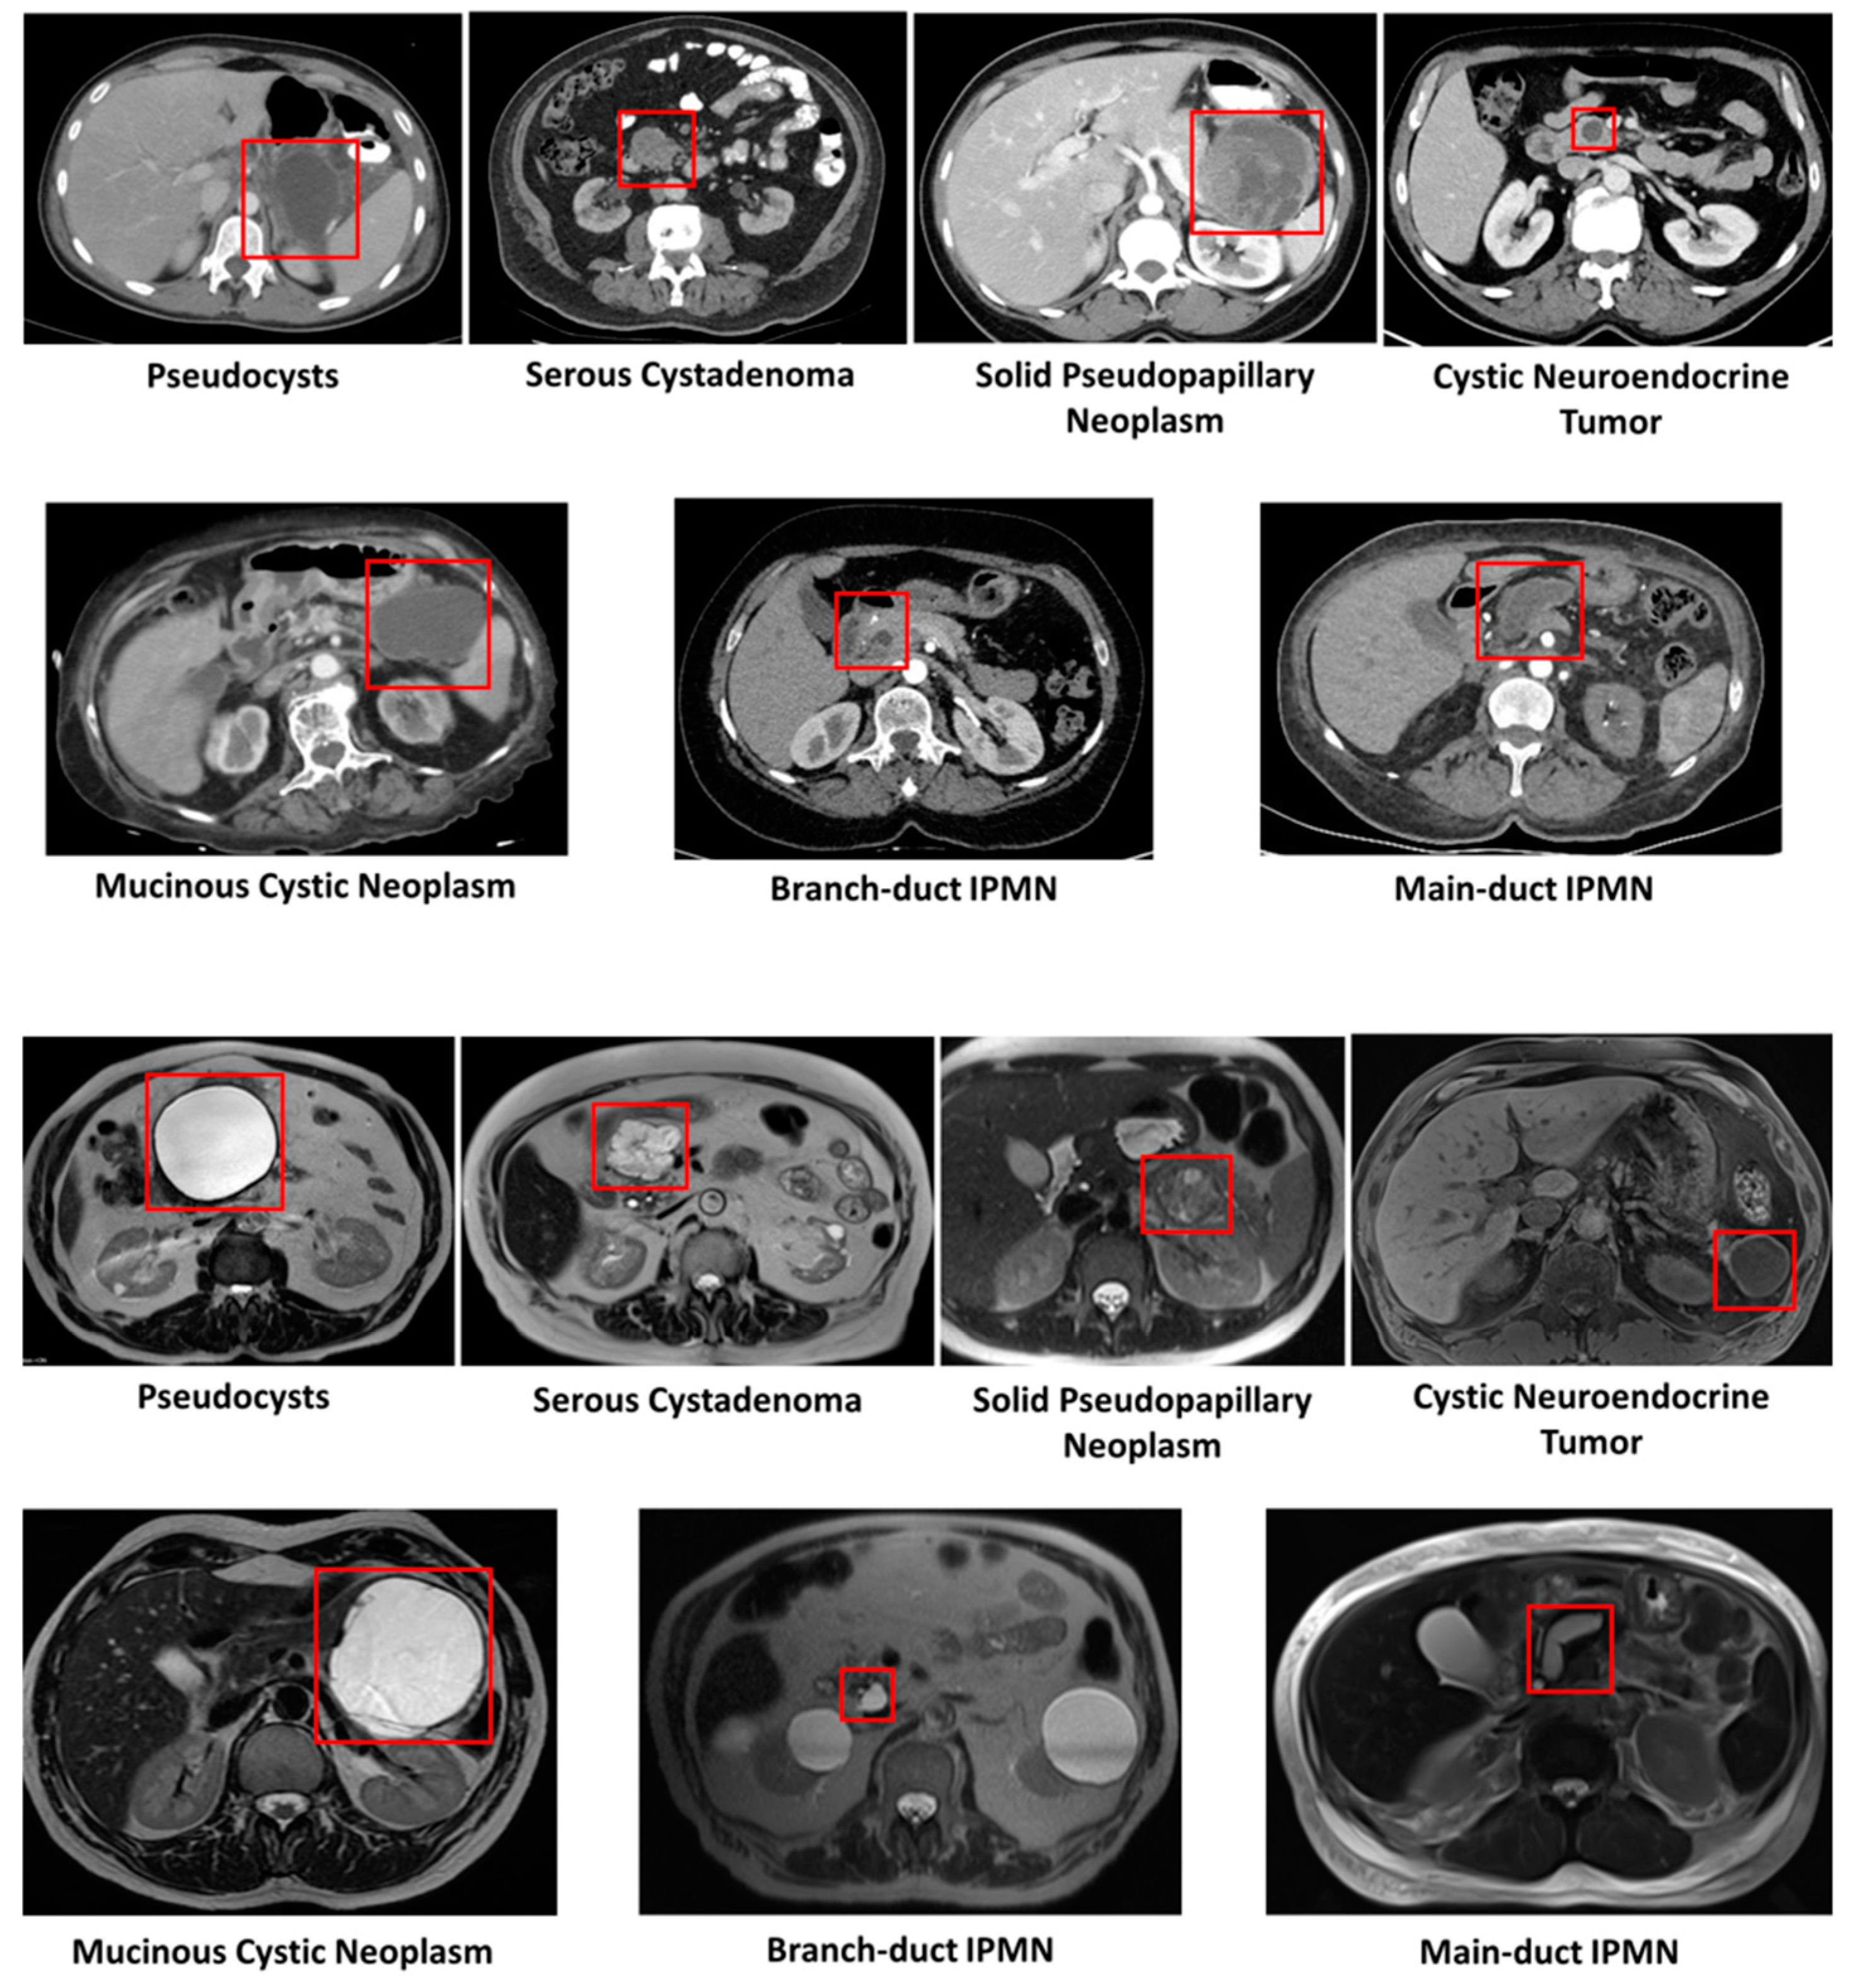

2.2. Radiological Properties of PCLs

5.1.2. CT-Based PCL Diagnosis with AI and Radiomics

5.1.3. MRI-Based Studies (Segmentation and Diagnosis)

5.1.4. Segmentation of Pancreas from MRI